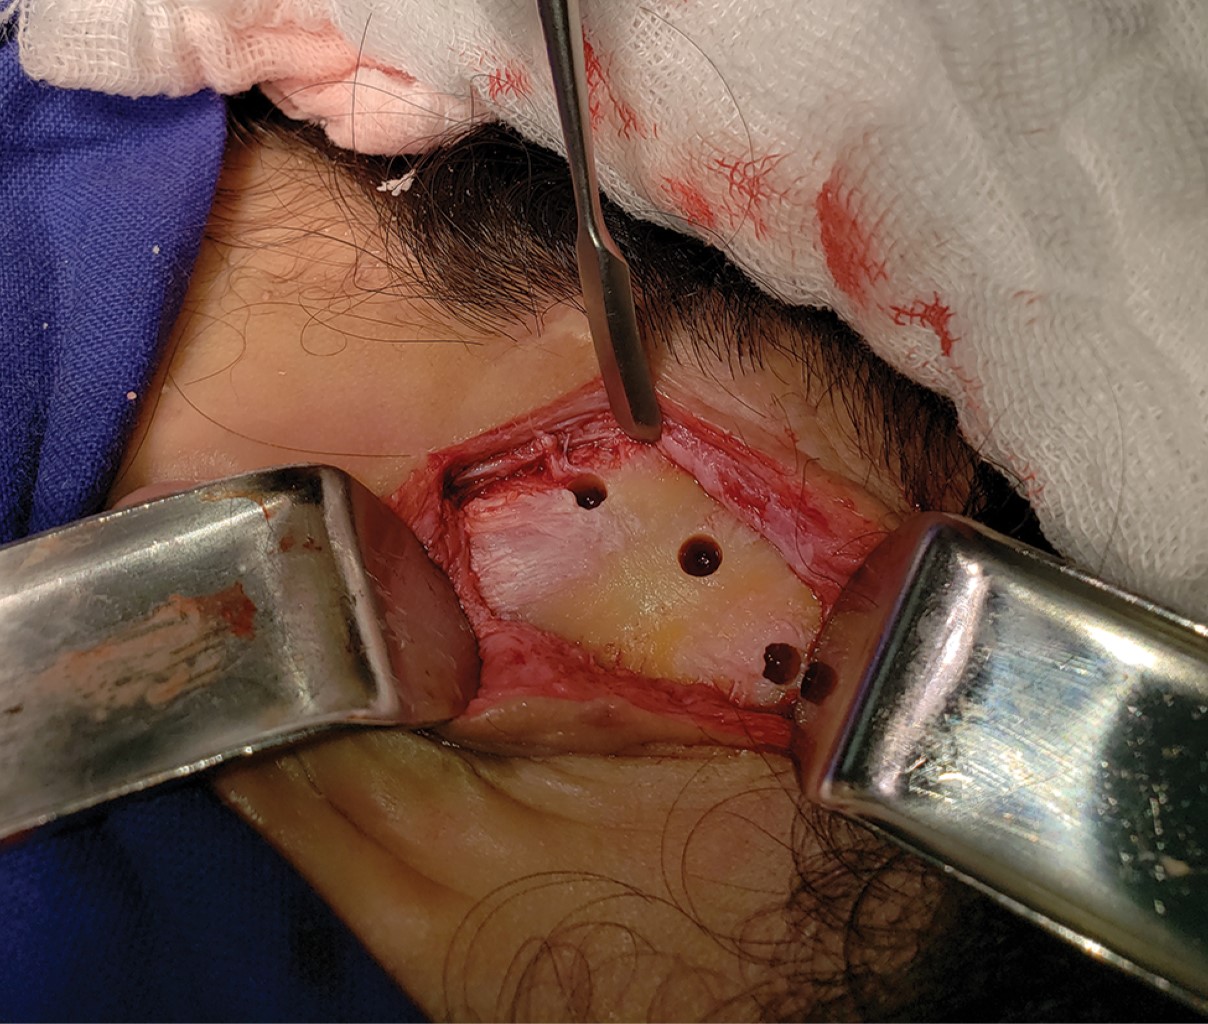

Paciente masculino de 26 años de edad, asiste a consulta de cirugía maxilofacial por fracaso en cirugía de reconstrucción auricular con injerto costocondral, se realizó la historia clínica completa del paciente el cual refiere "inconformidad estética". En el examen clínico se observa microtia en pabellón auricular derecho grado III de Marx (Figura 1) en donde se aprecia un esbozo de cartílago amorfo. Se registró la medida del pabellón auricular contralateral para determinar la medida de la prótesis, dando un total de 62 mm, esto con el fin de tener un resultado armónico y simétrico, Se comenzó con la planeación quirúrgica y se analizó detalladamente la tomografía para evaluar el espacio disponible para los implantes; se registraron medidas de hueso disponible en los distintos cortes tomográficos (Figura 2), así como de tejido blando, lo que permite seleccionar el pilar implantológico adecuado para el caso. Se realizó un modelo estereolitográfico en donde se midió el área disponible para la colocación de implantes; en este caso se planeó la colocación de tres implantes a 13 mm de distancia del conducto auditivo externo (CAE): posteriormente se realizó la cirugía en el modelo estereolitográfico (Figura 3) para poder analizar el resultado y se fabricó una guía para la colocación de implantes que permitiera posicionarlos a las 7, a las 9 y a las 11, a 13 mm de distancia del CAE. En el acto quirúrgico se realizó una incisión retroauricular hecha a 50 mm del CAE para exponer la porción mastoidea del hueso temporal en donde se colocó la guía quirúrgica (Figura 4). Se realizó el protocolo de fresado para implantes 4.1 × 6 mm (Figura 5) y se insertaron los implantes en su posición, a un torque final mínimo de 45 nm (Figura 6) se colocaron los tornillos tapa de los implantes y, por último, se remodeló el cartílago preexistente y se suturó el lecho quirúrgico con nylon 5-0 (Figura 7). Se llevó un control postoperatorio durante los siguientes cuatro meses para evaluar la completa osteointegración de los implantes.

Figura 4